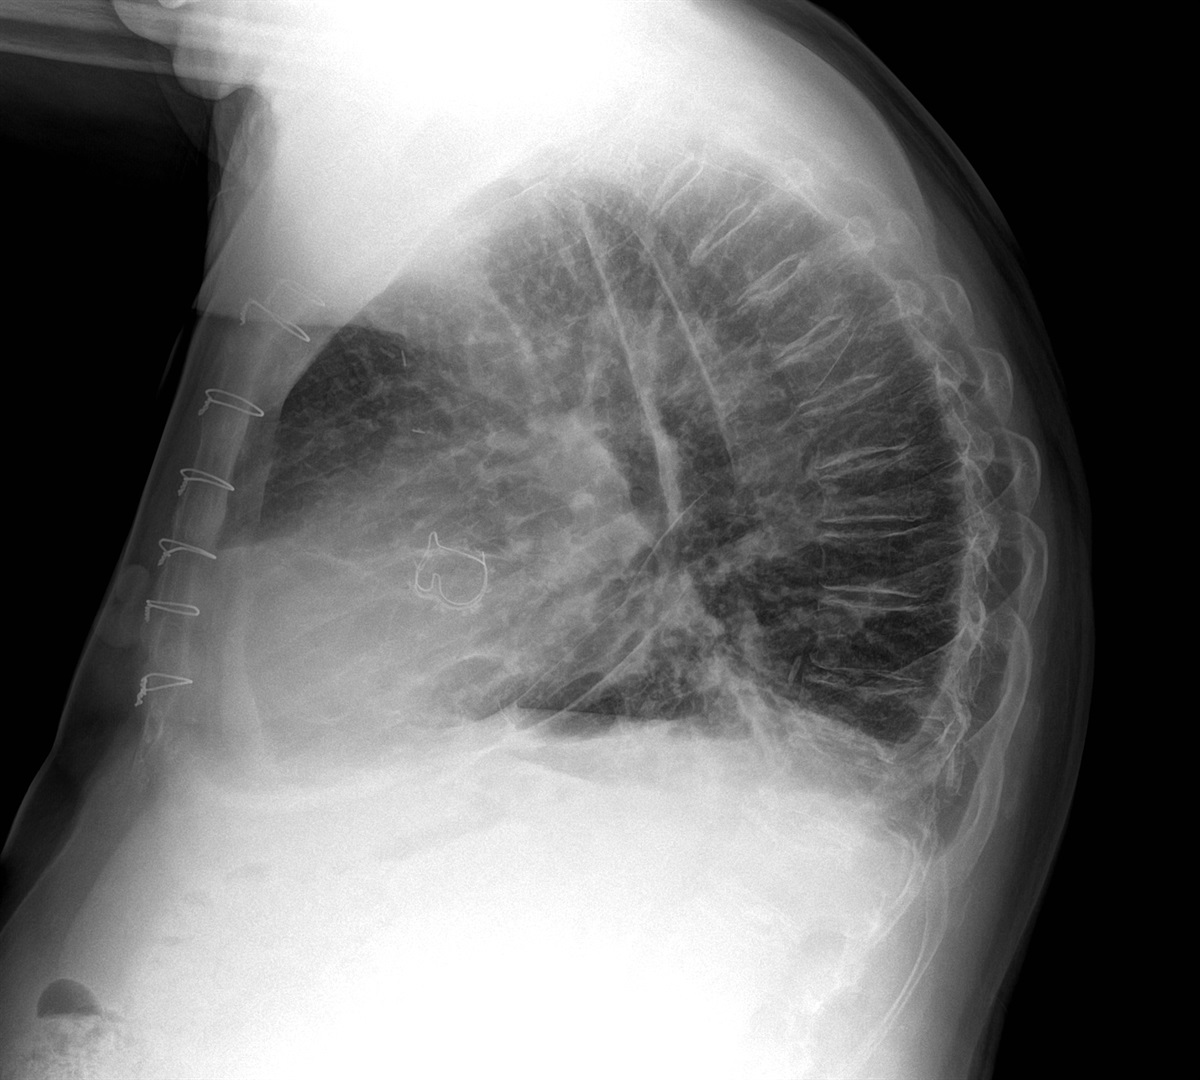

Pericardial agenesis (partial) is a rare cardiac defect. Radiologically, it presents with the following :

levoposition of the heart

prominent pulmonary artery

air interface in the aorto-pulmonary window or between the base of the heart and the diapgragm

CT-scan is better than MRI for this diagnosis, since it has better spatial resolution. The pericardial defect will be seen. A complete pericardial defect is a benign condition, while patients with partial agenesis may have cardiac herniation through the defect. They should be managed surgically.

* **Case courtesy of Dr Maxime St-Amant, Radiopaedia.org, rID: 20695**